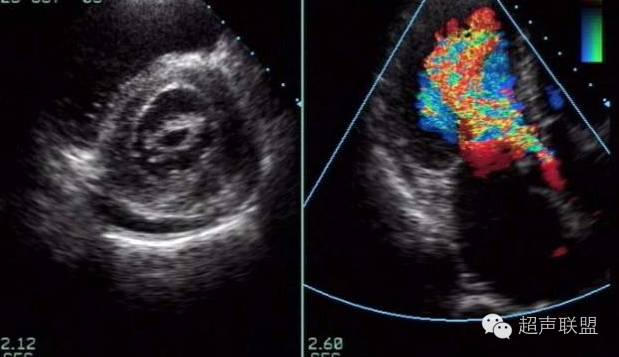

2维超声

阳性所见特异性强是定量诊断的主要依据之一。二尖瓣结构增厚,纤维化和钙化使其回声增强,尤其瓣尖部分可呈团状回声,腱索粘连,缩短及肌肥厚,胸骨旁左室短轴二尖瓣水平可观察到瓣叶交界处粘连情况。二尖瓣活动受限的典型实时图象表现为前叶呈圆顶状运动,开放时瓣体向室间隔方向运动,带动钩状瓣尖呈垂直方向运动,后叶与前叶呈同向运动。

二尖瓣开放幅度小及瓣口面积变小是超声诊断二尖瓣狭窄的最主要依据之一。目前通过两种常用方法:

①2维超声:左室短轴二尖瓣口水平可直接测定二尖瓣口的实际瓣口面积,可作为狭窄严重性的判断依据。